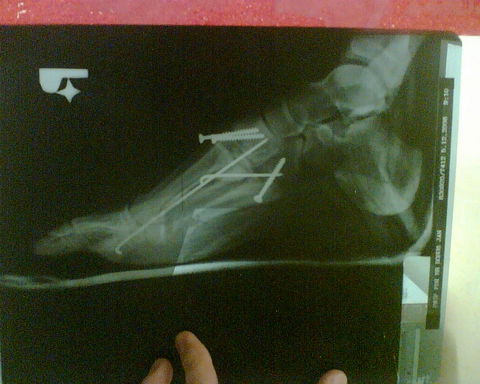

-> pistaa: co si robil? mne sa len 2x podarilo vytknut clenok, ale taky sikovny aby mi to museli srobovat som neni